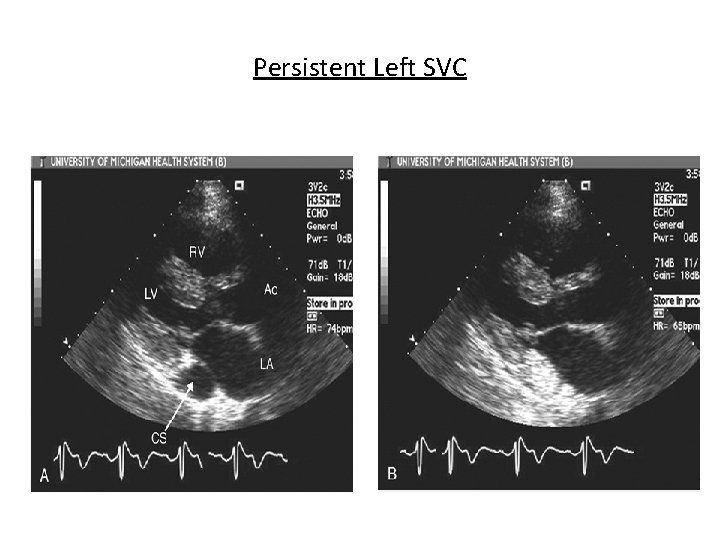

Persistent Left SVC

Shunt Detection • Right-to-left shunts - agitated saline - agent of choice – Atrial septal defects of all types – Patent foramen ovale - Valsalva and cough – Pulmonary arteriovenous malformations - 5 to 15 cycles – Larger ventricular septal defects during diastole – Left SVC • Left-to-right shunt – Negative contrast effect